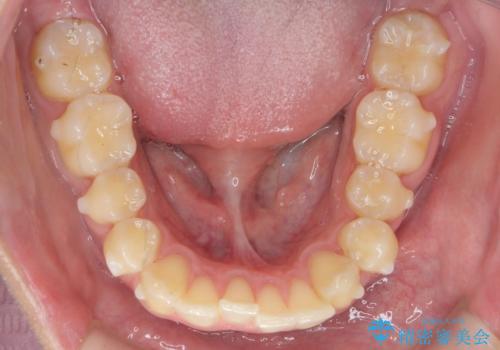

過蓋咬合・上顎前突・叢生を改善するマウスピース矯正

・前歯の深い噛み合わせ (過蓋咬合)

・上顎前突(Angle Class2)

・叢生(がたつき)

以上のような問題点をマウスピース矯正インビザラインとマイクロインプラントを用いて矯正治療を行い改善して行きます。

20時間以上のマウスピース装着、ゴムかけを遵守していただいたおかげでしっかりと噛み合わせ、がたつきの改善を行うことができました。